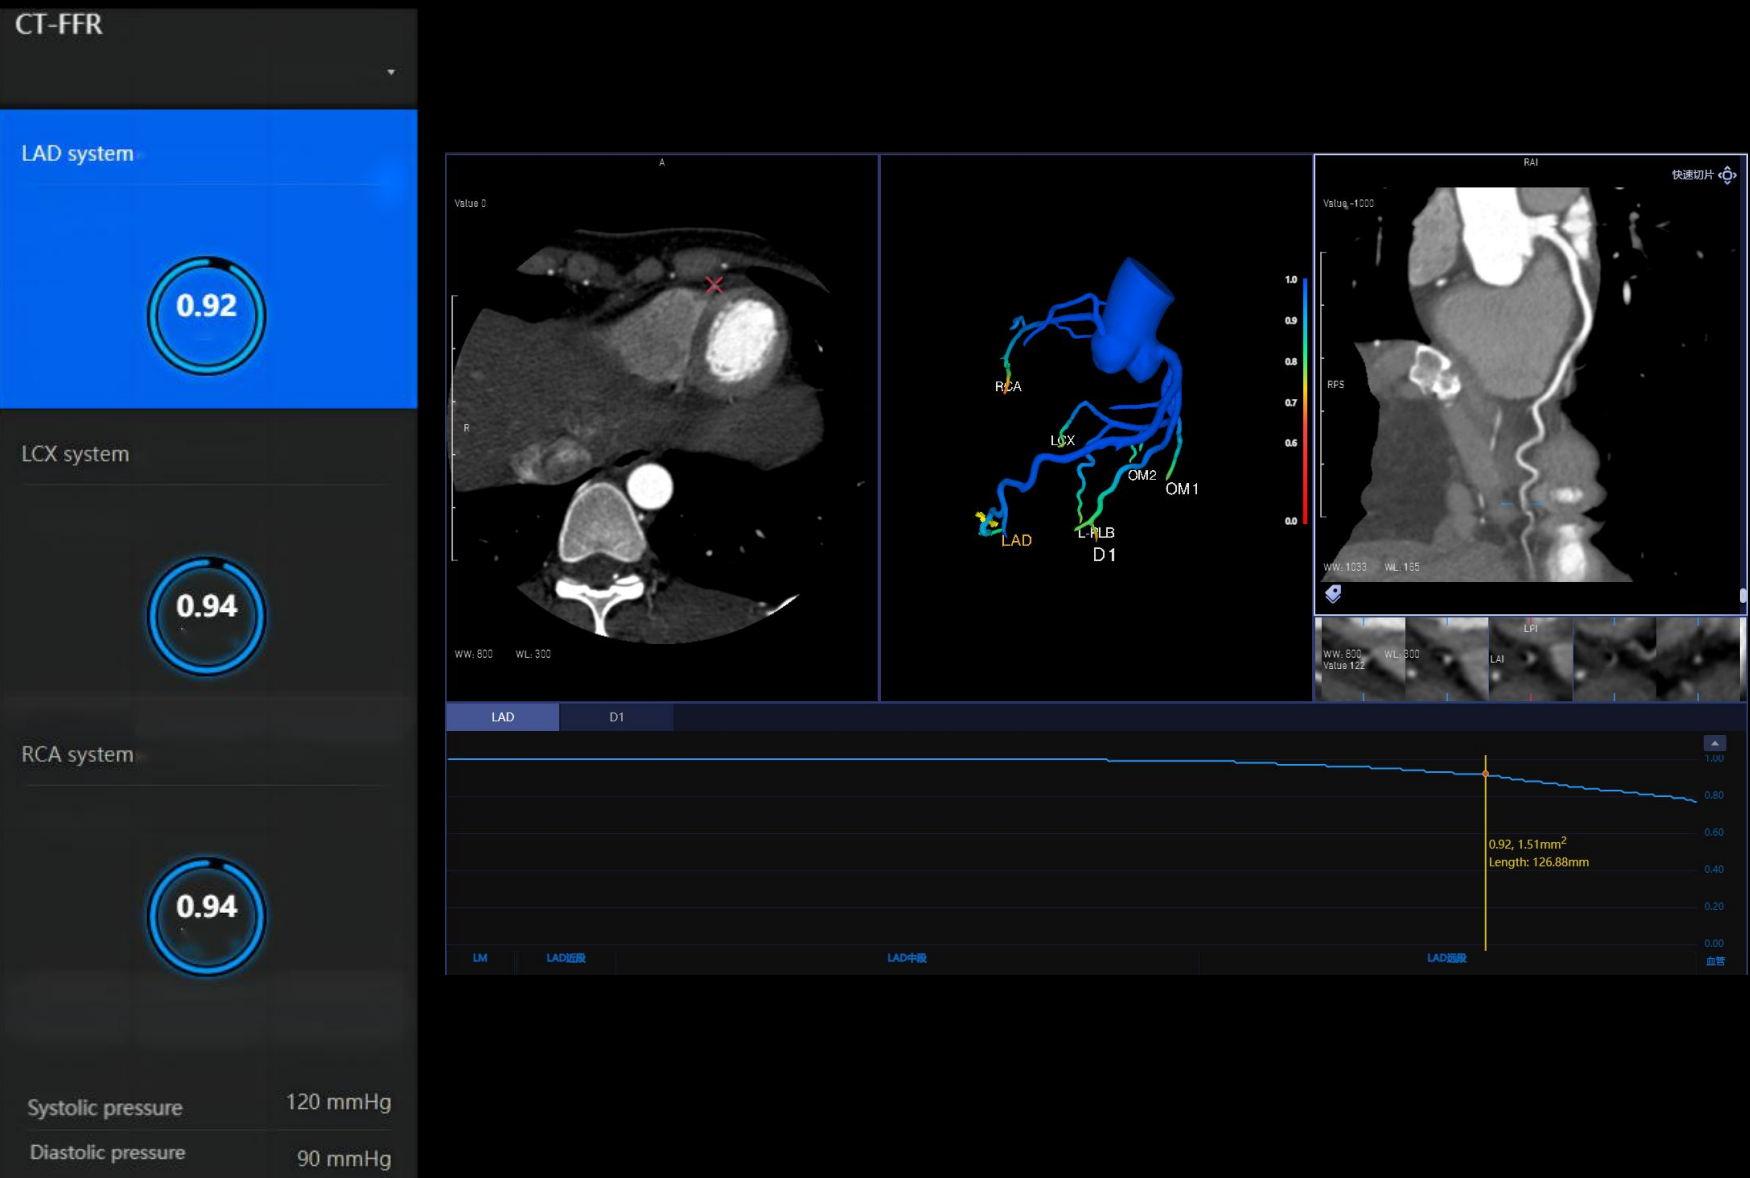

Hệ thống CT tiên tiến này sở hữu tốc độ quay siêu nhanh 0,286 giây, bóng tia X công suất 7,5 MHU (hiệu dụng lên đến 27,1 MHU) cùng detector độ rộng 40 mm. Nhờ các công nghệ hiện đại, hiệu suất chụp tim vượt trội được nâng lên một chuẩn mực mới, mang lại hình ảnh tim mạch chính xác và ổn định. Thiết bị tích hợp nền tảng AI toàn diện, bao phủ toàn bộ quy trình từ định vị bệnh nhân, quét, kiểm soát liều, giảm nhiễu và triệt tiêu artefact đến hậu xử lý hình ảnh và hỗ trợ chẩn đoán, đảm bảo độ chính xác vượt trội ngay cả trong những tình huống lâm sàng phức tạp nhất.

Chỉ với 1 click tự động xác định chính xác phạm vi quét theo giao thức đã chọn, giảm thiểu điều chỉnh thủ công phức tạp

Chỉ với 1 click định vị chính xác iso-center, tối ưu hình ảnh và liều tia, giảm thiểu phơi nhiễm